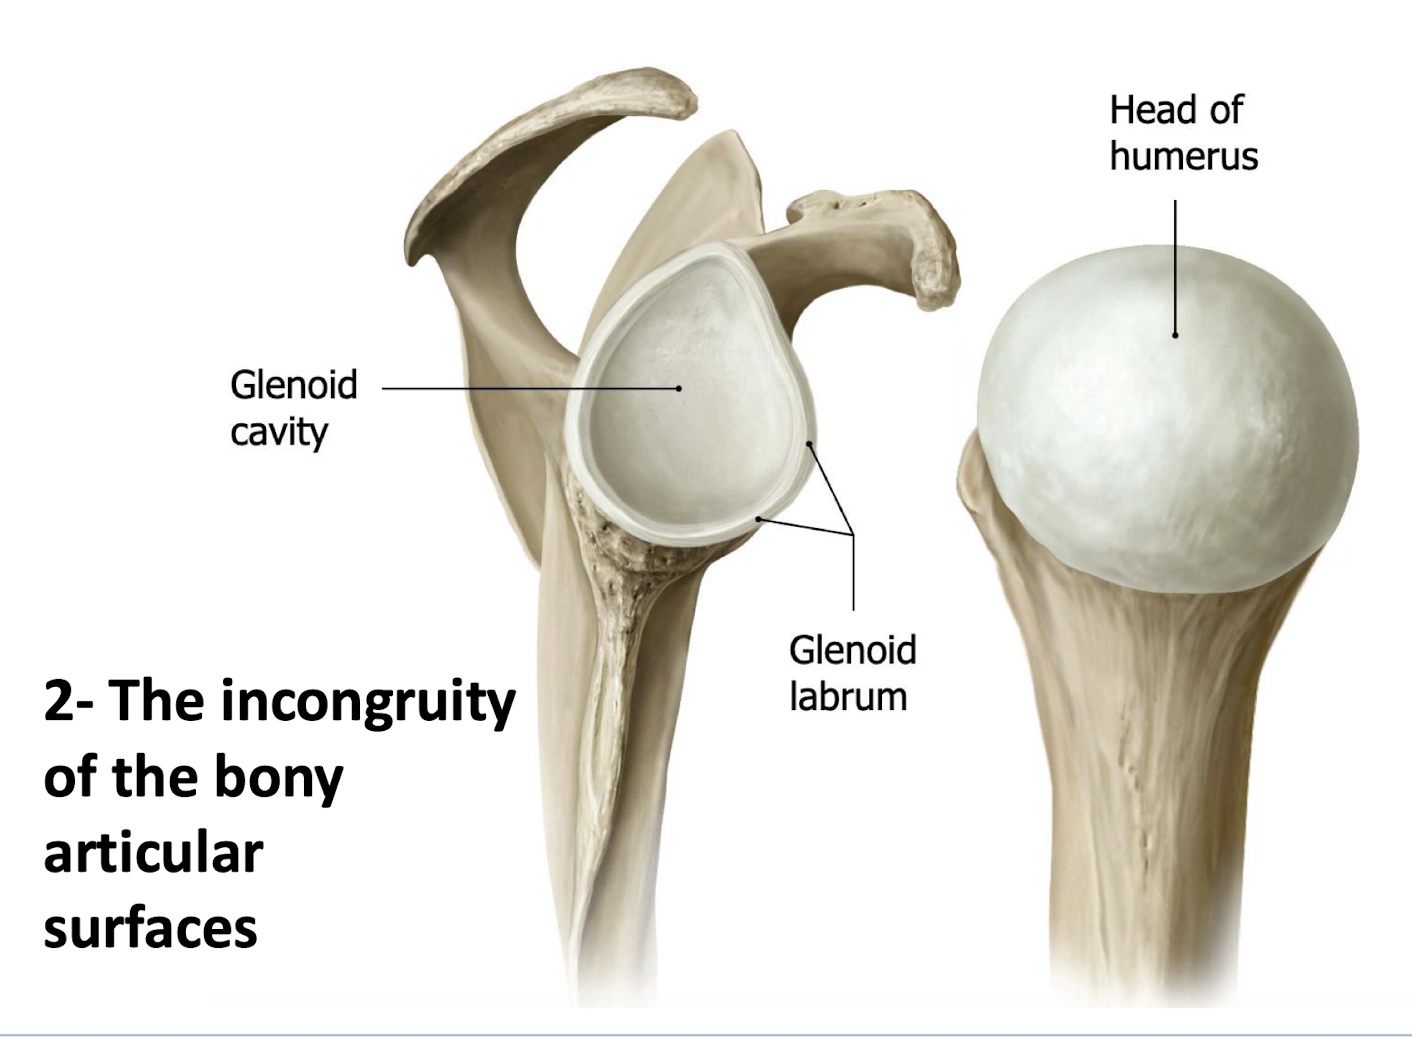

What structure deepens the shallow, oval articular surface of the glenoid fossa?

A cartilaginous labrum.

The glenohumeral joint is formed by the articulation of which two structures?

The head of the humerus and the glenoid fossa of the scapula.

What two factors contribute to the impressive mobility, yet inherent instability, of the glenohumeral joint?

The thin, lax articular capsule and the incongruity of the bony articular surfaces.